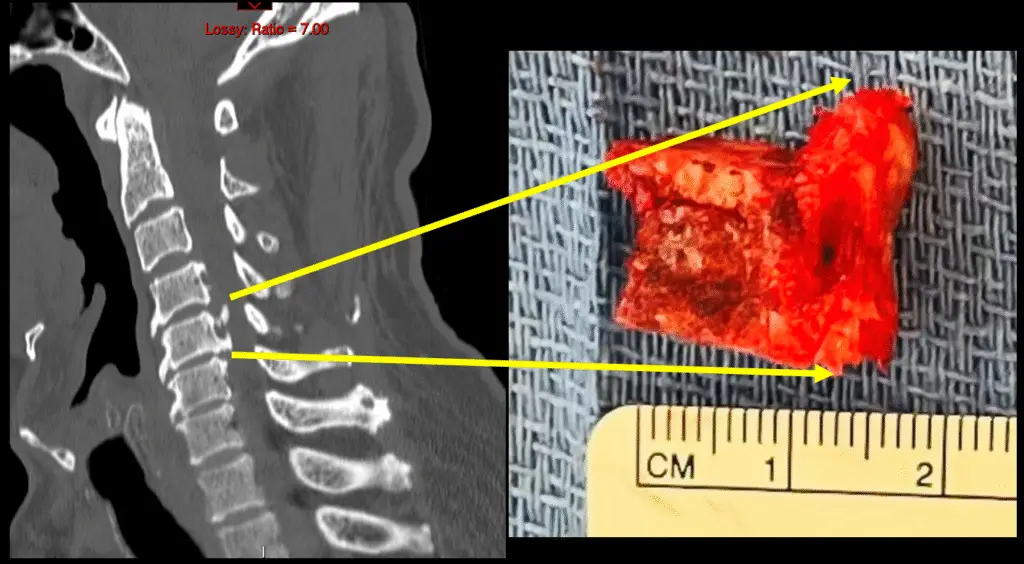

Cervical Corpectomy for Tumor

Anterior Cervical Corpectomy and Fusion

c5 corpectomy ct

c5 corpectomy

anterior cervical c5 corpectomy and fusion